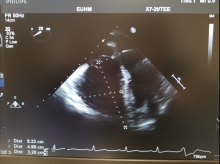

Surgical pulmonary embolectomy (SPE) is a safe and effective therapeutic approach to pulmonary embolism management for patients who are diagnosed with submassive and/or massive acute pulmonary emboli by clinical exam, supported by computed tomography (CT) and echocardiographic assessment. Other indications for surgical embolectomy include presence of thrombus-in-transit, concomitant cardiac pathology such as a large patent foramen ovale, or relative contraindications to thrombolytic therapy, including recent cerebrovascular or intracranial pathology, recent surgery, active bleeding, or other absolute contraindications to anticoagulation.

When such a patient presents to the authors, they activate their Pulmonary Embolectomy Response Team (PERT) and share a brief clinical resume, inclusive of pertinent clinical findings and CT and echo images. Accordingly, the multidisciplinary team, which includes CT surgeons, interventional cardiologists, vascular surgeons, pulmonologist, intensivists, and hematologists deliberate in order to reach a consensus on the best therapeutic approach.

- Use the Seldinger technique to access the common femoral vein as follows: Access the vein with a needle and subsequent wire. Serially dilate the vessel to the size of the cannula. Insert venous cannula (25 French venous cannula) and position within the right atrium under TEE guidance. Connect venous line to bypass circuit.

- TEE availability